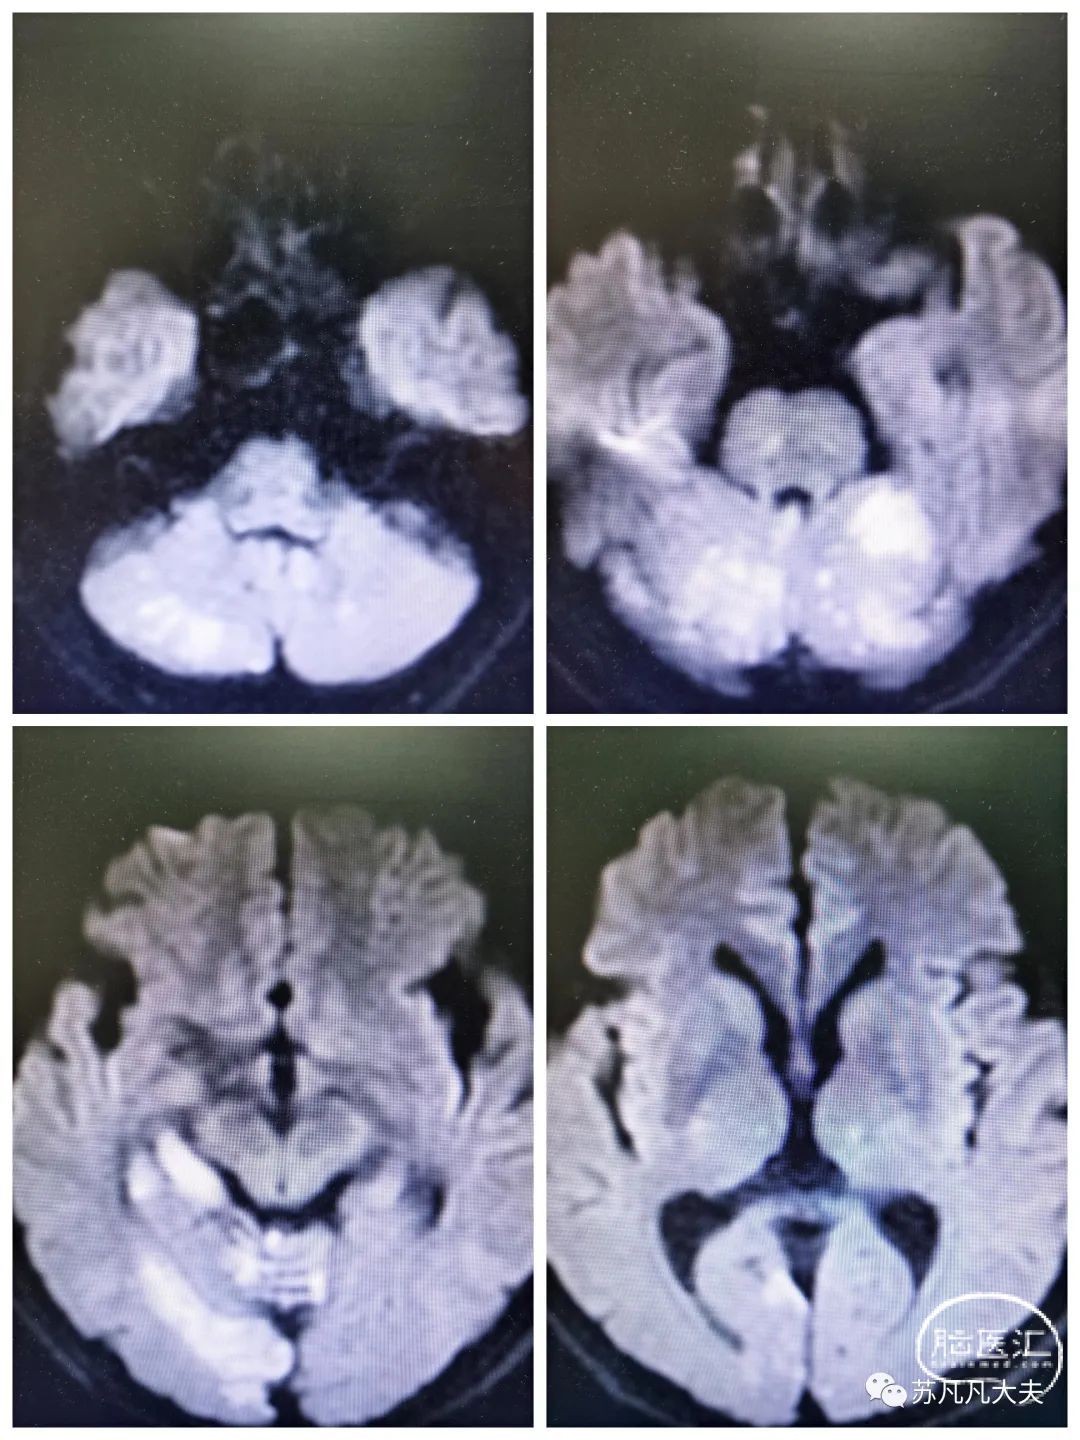

核磁DWI示双侧小脑,右侧颞叶,岛叶,双侧顶枕叶多发脑梗死。(19:30)

MRA示右侧椎动脉未显影,左侧大脑后动脉未显影。